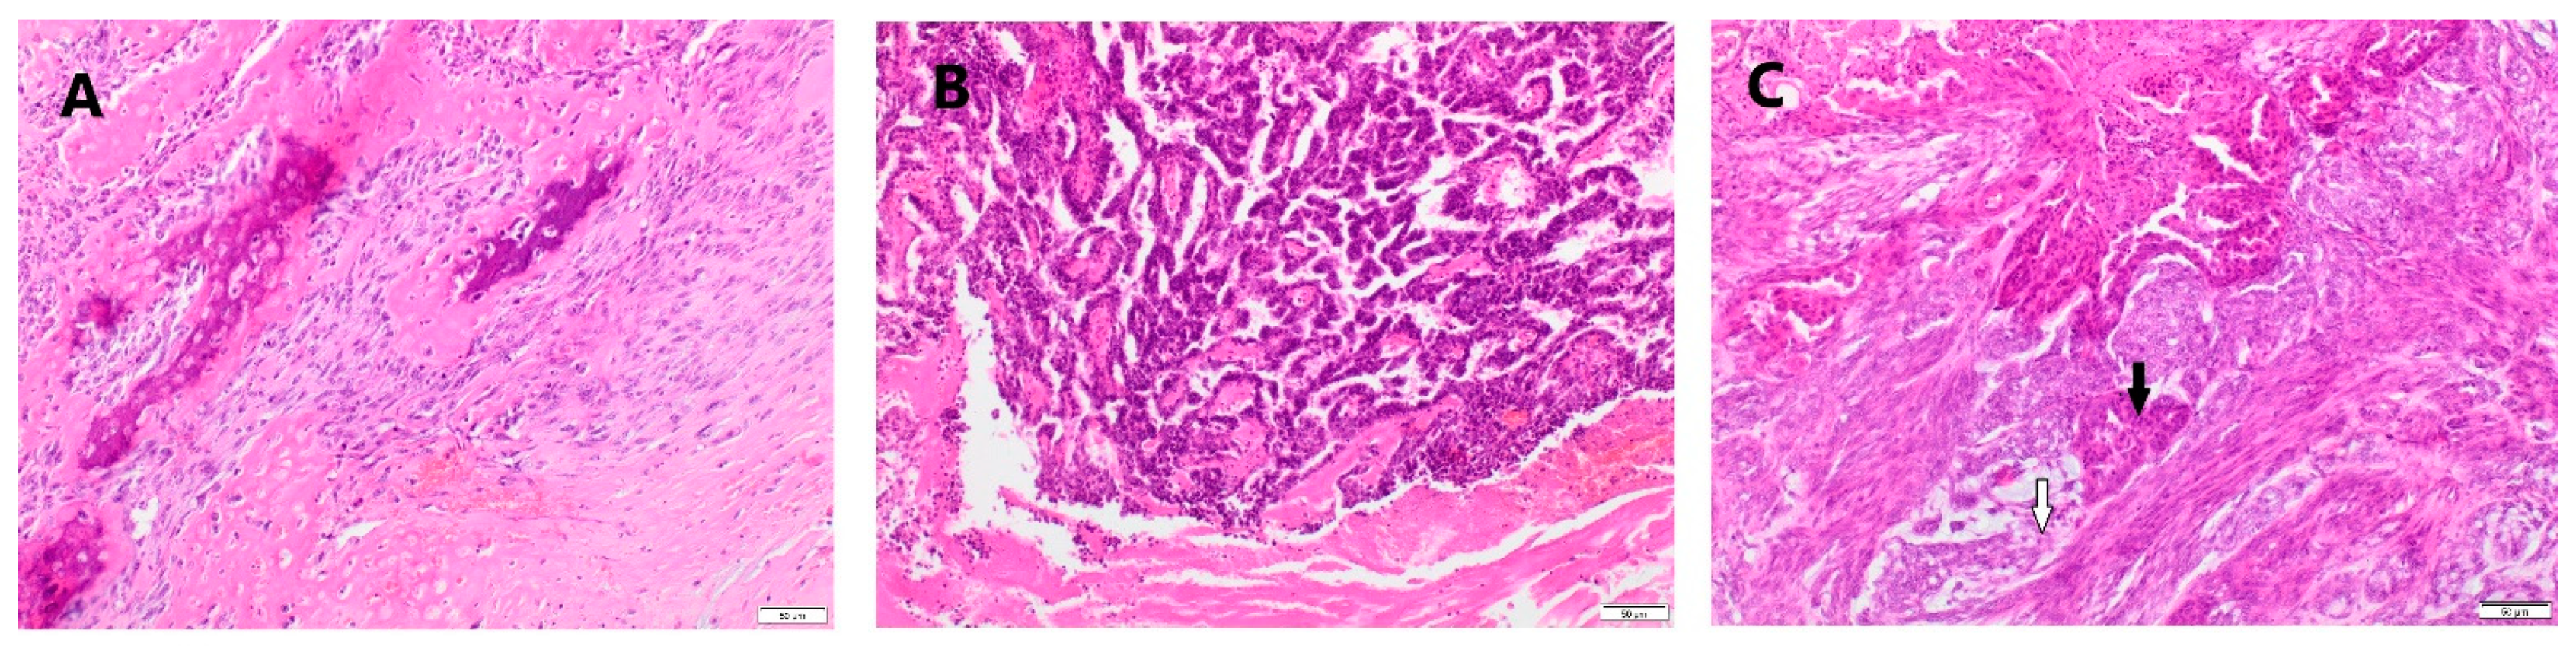

2.2. Histological Examinations of Tumor Samples